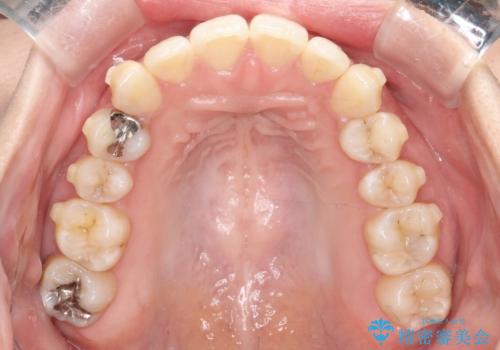

- 前歯のでこぼこが気になると来院されました。

奥歯の噛み合わせは綺麗に噛んでいたため、前歯の叢生(でこぼこ)を、短期間で治療完了するように計画しました。

奥歯の噛み合わせは整っていたため、前歯の並びを美しく修正することに専念できました。マウスピース矯正による治療で短期間で改善しました。

前歯のガタツキを改善する治療法として、マウスピース矯正が適していることが多いです。